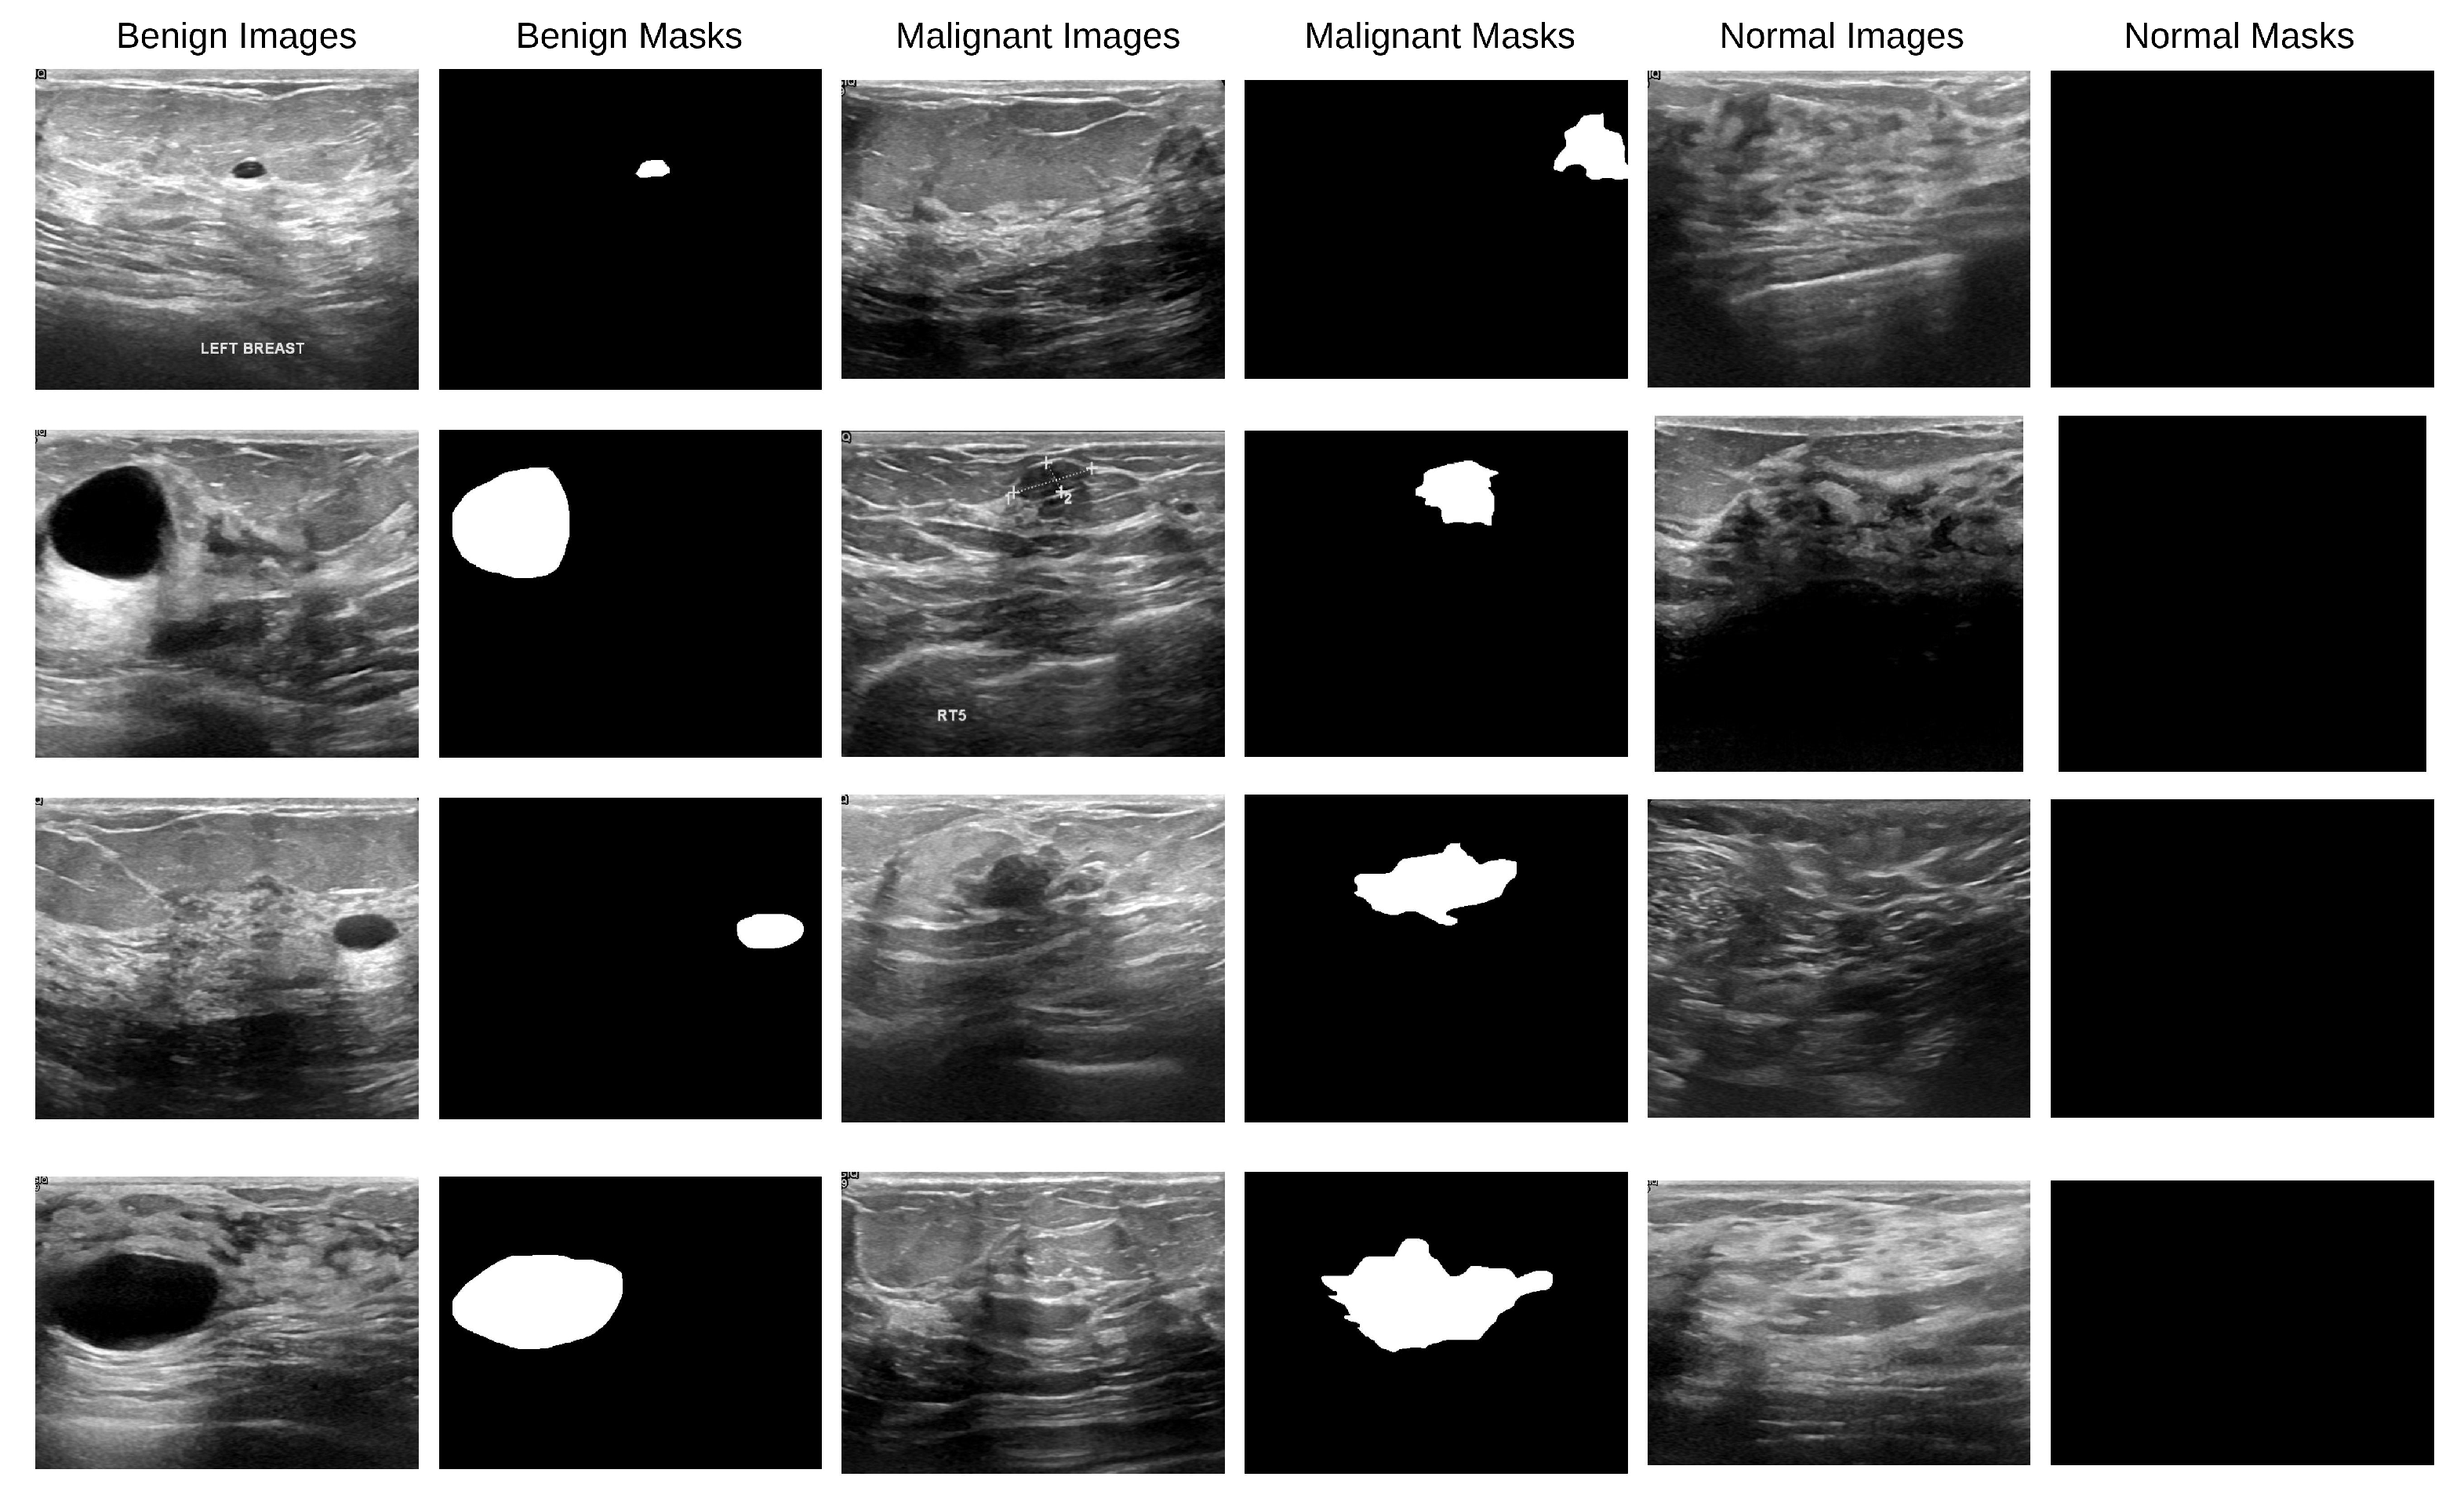

A total of 780 ultrasound images obtained at Baheya Hospital in Cairo, Egypt, using LOGIQ E9 and LOGIQ E9 Agile ultrasound scanners are included in the Breast Cancer Ultrasound Images (BUSI) dataset [37]. Women aged 25 to 75 years old had their breast ultrasound images included in the baseline data. There were 600 female patients. All of the images in the collection, moreover, are saved as PNG files and have an average resolution of 500 × 500 pixels. A binary ground-truth mask that identifies tumor locations is included with each image, and the images have been divided into three categories: normal (133 photos), benign (437 images), and malignant (210 images). With a significant number of ultrasound pictures classified as normal, benign, and malignant cases of various nodule sizes and shapes, the BUSI dataset is a useful and difficult resource for breast lesion segmentation research. Figure 2 displays the data sample.

Figure 2. BUSI dataset images along with their corresponding binary ground-truth masks.